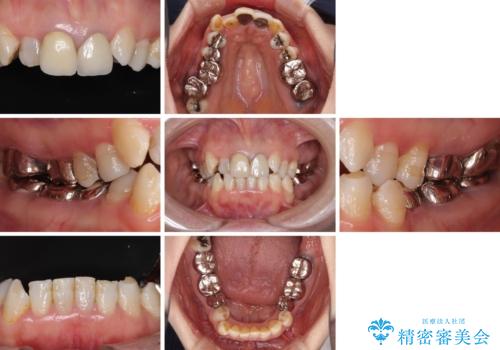

- 全顎的な歯列不正と、銀歯だらけの奥歯を気にして来院された患者様です。

奥歯の銀歯は、セラミッククラウンを装着するには歯の高さが不十分であり、そのままでは矯正治療を行うことが困難であるため、歯冠長延長術を行うこととしました。

また、根管治療の必要な歯がいくつかあるため、歯周外科治療の治癒期間を利用して根管治療を行い、その後インビザラインにて矯正治療を行うこととしました。

矯正治療後にはオールセラミッククラウンにて補綴治療を行うこととしました。

外科処置に対する恐怖心が強かったため、処置の際には静脈内鎮静法を用いて、リラックスした状態で行いました。